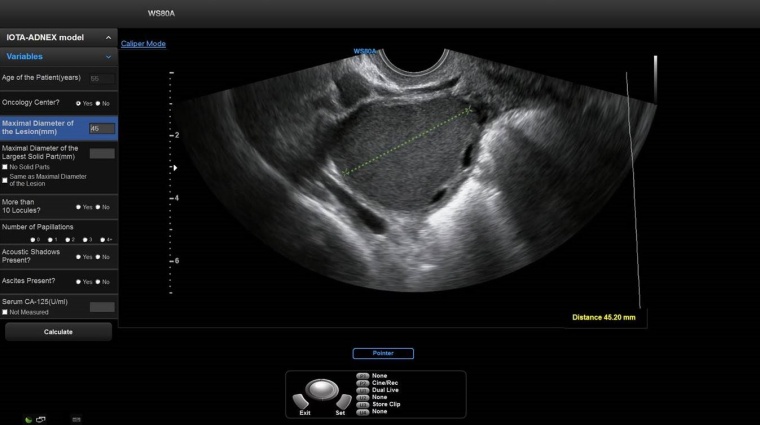

Das ADNEX-Risikomodell der IOTA-Gruppe (International Ovarian Tumour Analysis) kann von Ärzten verwendet werden, um Eierstockkrebs bei Frauen mit mindestens einem persistierenden adnexalen Tumor zu diagnostizieren.

ADNEX schätzt die Wahrscheinlichkeit, dass ein adnexaler Tumor gutartig, grenzwertig, Stadium I, Stadium II–IV oder sekundärer metastasierender Krebs ist. Im Interview erläutern die IOTA-Mitglieder Prof. Dr. Dirk Timmerman vom Universitätsklinikum Leuven und Dr. David Hartge, Oberarzt und Lehrbeauftragter am Universitätsklinikum Schleswig-Holstein in Lübeck, die Vorteile des Modells und die Rolle der IOTA-Gruppe in der modernen Gynäkologie.

Samsung hat das IOTA-ADNEX-Modul in ein Ultraschallsystem integriert. Glauben Sie, dass dies zu einem Unterschied in der Diagnostik führen wird?

Dr. David Hartge: Um neue Techniken anwenden zu wollen, müssen sie zunächst einmal bekannt sein, verfügbar sein und einen Mehrwert bringen. Je nach Expertise des Untersuchers können verschiedene Modelle zur Anwendung kommen. Viele Fragestellungen wären schon im Niedergelassenenbereich lösbar. Eine mögliche Konsequenz der zusätzlichen Anwendung von IOTA-basierten Modellen könnte sein, dass sich die diagnostische Sicherheit flächendeckend verbessert und weniger Patientinnen unnötigerweise zur Abklärung von unklaren Befunden an Zentren weiterverwiesen werden müssen.

Stattdessen könnte sich der Anteil der tatsächlich behandlungsbedürftigen Patientinnen, die an Zentren überwiesen werden, erhöhen. Es könnten somit unnötige Untersuchungen für unsere Patientinnen vermieden und gleichzeitig die Arbeit an Zentren effektiver gestaltet werden. Unsere Patientinnen könnten schließlich durch weniger Verunsicherung und raschere Behandlung profitieren.■